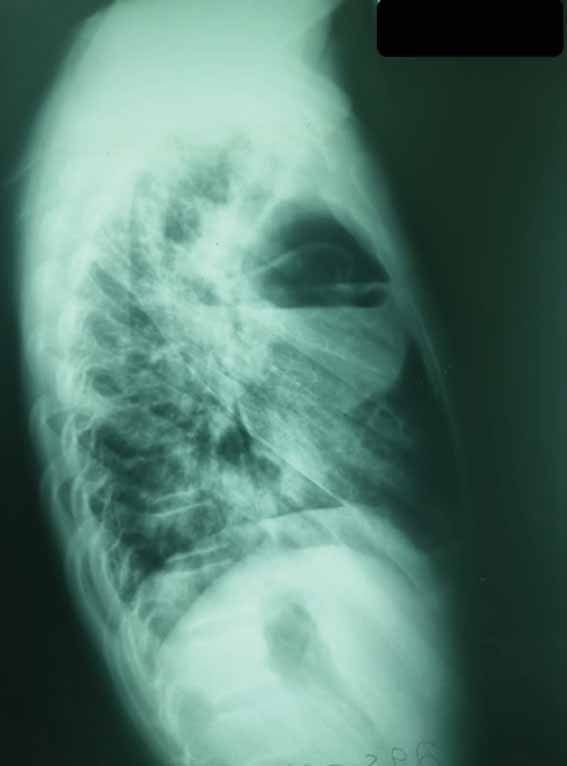

Các đặc điểm chính của nang sán trên hình ảnh X-quang bao gồm: dấu meniscus, dấu bán nguyệt, dấu Cumbo, dấu vỏ hành tây, dấu hoa súng và dấu khối trong khoang. Một trong những dấu hiệu kinh điển trên hình ảnh X-quang của nang sán là một vùng sáng tròn rõ ràng trong phổi, có hoặc không có sự vôi hóa(Hình 6). Bệnh nang sán phổi có thể bị nhiễm trùng thứ phát và trên hình ảnh X-quang ngực có thể xuất hiện u nang và mức dịch khí (Hình 7).

|   Hình 7.Hình ảnhX-quang ngực nghiêng cho thấy mức dịch khí bên trong một nang sán đã tồn tại từ trước gợi ý  nhiễm trùng chồng lấn.